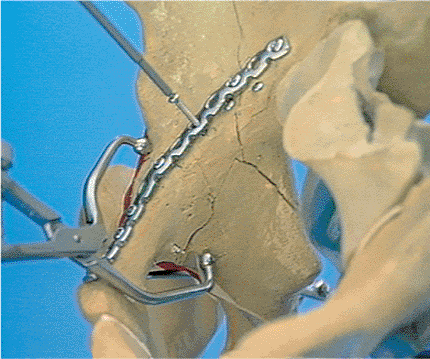

![]() |

Figure 42.23.

Farabeuf and Weber clamps are used to reduce the anterior column fracture. Note that the fracture fragment from the pelvic brim has been reduced and fixed with a single screw. The accurate reduction of the anterior column is not possible unless the two extra-articular fracture fragments are accurately reduced and stabilized. (Reprinted with permission from AO/ASIF, Both Column Fracture Through the Ilioinguinal Approach [Video]. Copyright © AO/ASIF Video, 1991.

) |

Figure 42.26.

Curved pelvic plate is contoured to the innominate bone. Shown is the concavity at the superior ramus, the convexity at the pectineal eminence, and the concavity of the internal iliac fossa. (Reprinted with permission from AO/ASIF, Both Column Fracture Through the Ilioinguinal Approach [Video]. Copyright © AO/ASIF Video, 1991.

Figure 42.27.

Posterior column fracture is reduced with the use of an angled reduction clamp placed entirely within the second window of the approach. The iliopsoas and femoral nerve are retracted laterally, the external iliac vessels are retracted laterally, and the external iliac vessels are retracted medially. One point of the reduction clamp is on the anterior wall and the other is on the quadrilateral surface. (Reprinted with permission from AO/ASIF, Both Column Fracture Through the Ilioinguinal Approach [Video]. Copyright © AO/ASIF Video, 1991.

Figure 42.28.

Posterior column is held reduced with an angled reduction clamp. The screw is placed through the plate and parallel with the quadrilateral surface. (Reprinted with permission from AO/ASIF, Both Column Fracture Through the Ilioinguinal Approach [Video]. Copyright © AO/ASIF Video, 1991.